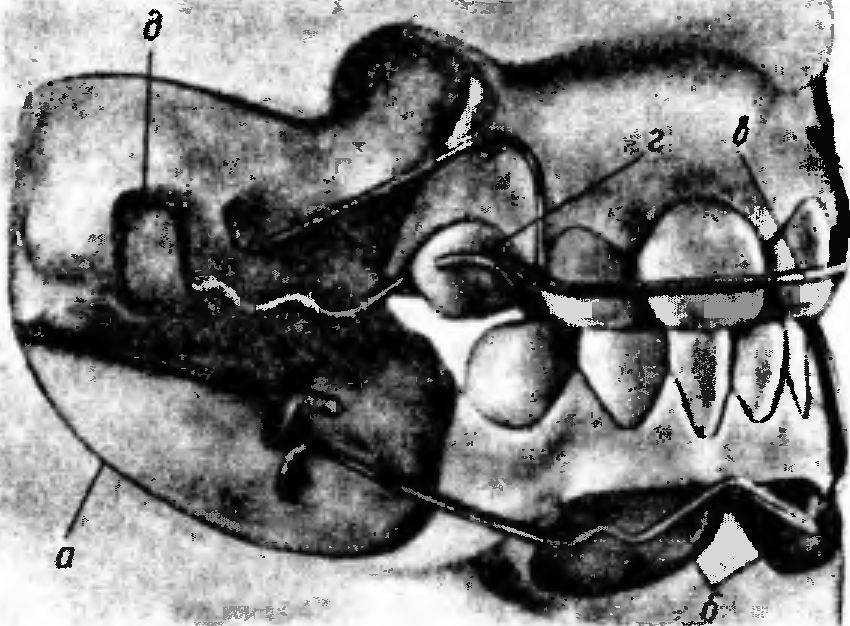

Рис. 241. Рабочие модели верхней и нижней челюстей в положении центральной окклюзии при дистальном прикусе.